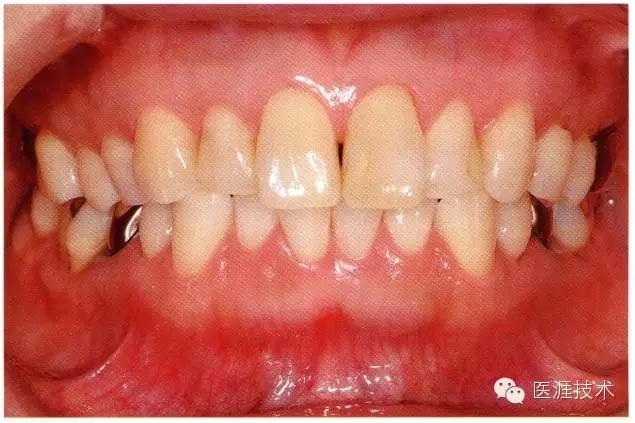

18歲男性的健康口腔內(nèi)部

圖為18歲男性,無特殊全身疾病,不抽煙。持續(xù)保養(yǎng)10年。牙菌斑控制比以前好,因刷牙稍稍過度臉頰側(cè)有牙齦萎縮傾向,但牙齒及牙周組織仍保健康。

28歲女性的健康口腔內(nèi)部

圖為28歲女性,無特殊全身疾病,不抽煙。10年前來院就診保養(yǎng)3年,期間中斷過,現(xiàn)又開始。齲壞風(fēng)險(xiǎn)高,當(dāng)初初診時(shí)已有好幾顆牙的鄰面有填充物,再填充了3牙的鄰面齲,現(xiàn)牙周組織健康。